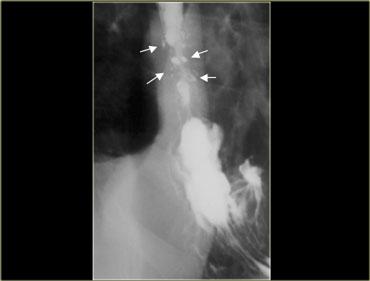

Bên trái: co bóp bậc ba ở lần nuốt đầu tiên (trái).

Co bóp nguyên phát bình thường ở lần nuốt tiếp theo (phải).

Các co bóp bậc ba này là những co bóp không có tính đẩy, thoáng qua và không liên tục, không cố định về vị trí và không kèm theo triệu chứng, thường gặp ở bệnh nhân cao tuổi.

A. Co bóp bậc ba không có tính đẩy ban đầu B. Ba hình ảnh trong quá trình thăm khám cho thấy các ổ đọng thuốc giống túi thừa C. Hình ảnh chụp muộn hơn trong quá trình thăm khám cho thấy các co bóp bậc ba đã biến mất

Đôi khi các co bóp bậc ba thoáng qua có thể giả dạng túi thừa.

Bên trái là hình ảnh của một bệnh nhân có co bóp bậc ba, trong quá trình thăm khám trông giống như túi thừa.